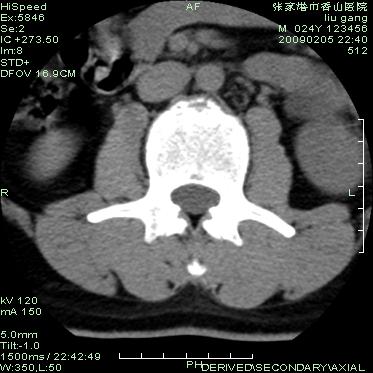

以下是引用hhcckk在2009-3-11 15:43:00的发言:[br]3、4、5腰椎及骶1椎体前上缘不规则,椎间隙改变不明显,结合患者年龄轻考虑:脊椎骨软骨病可能性大[br][br]脊椎骨软骨病又称青年性驼背(scheuerman)。[br][br]1964年sorenson首先提出x线影像学诊断标准:胸段脊柱至少3个相邻椎体有5°或5°以上楔形改变。椎体的楔形变是scheuermann病的基本特点,还可以有其它一些特征,如椎间隙变窄、schmorl结节、椎体终板变窄、不规则或扁平,顶椎前后径增长。

以下是引用随光逐影在2009-3-11 14:43:00的发言:[br]平片:l3、4、5及s1前上缘见类似“切角征”。[br]ct扫描:腰椎多个节段椎间盘向椎体内(椎体前部)突出。